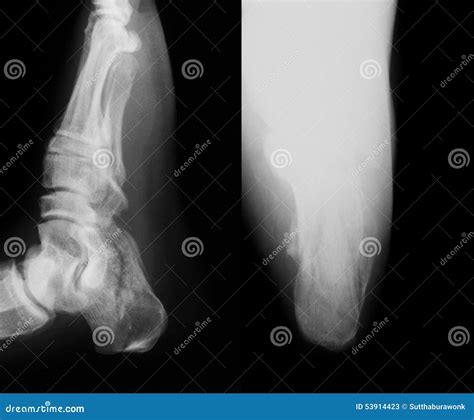

• Positioning: The patient is positioned on the X-ray table, and the affected foot is placed in a specific position to ensure clear visibility of the calcaneus. The technician may use supports or cushions to keep the foot in the correct position.

• Imaging: The X-ray machine is positioned over the foot, and multiple images are taken from different angles to provide a comprehensive view of the calcaneus. The technician may ask the patient to hold still and avoid moving during the imaging process.